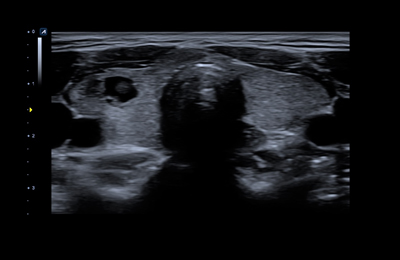

L8-17H

High density linear transducer(8-17MHz)

Application:

Breast, EM, MSK, Vascular, Small Parts